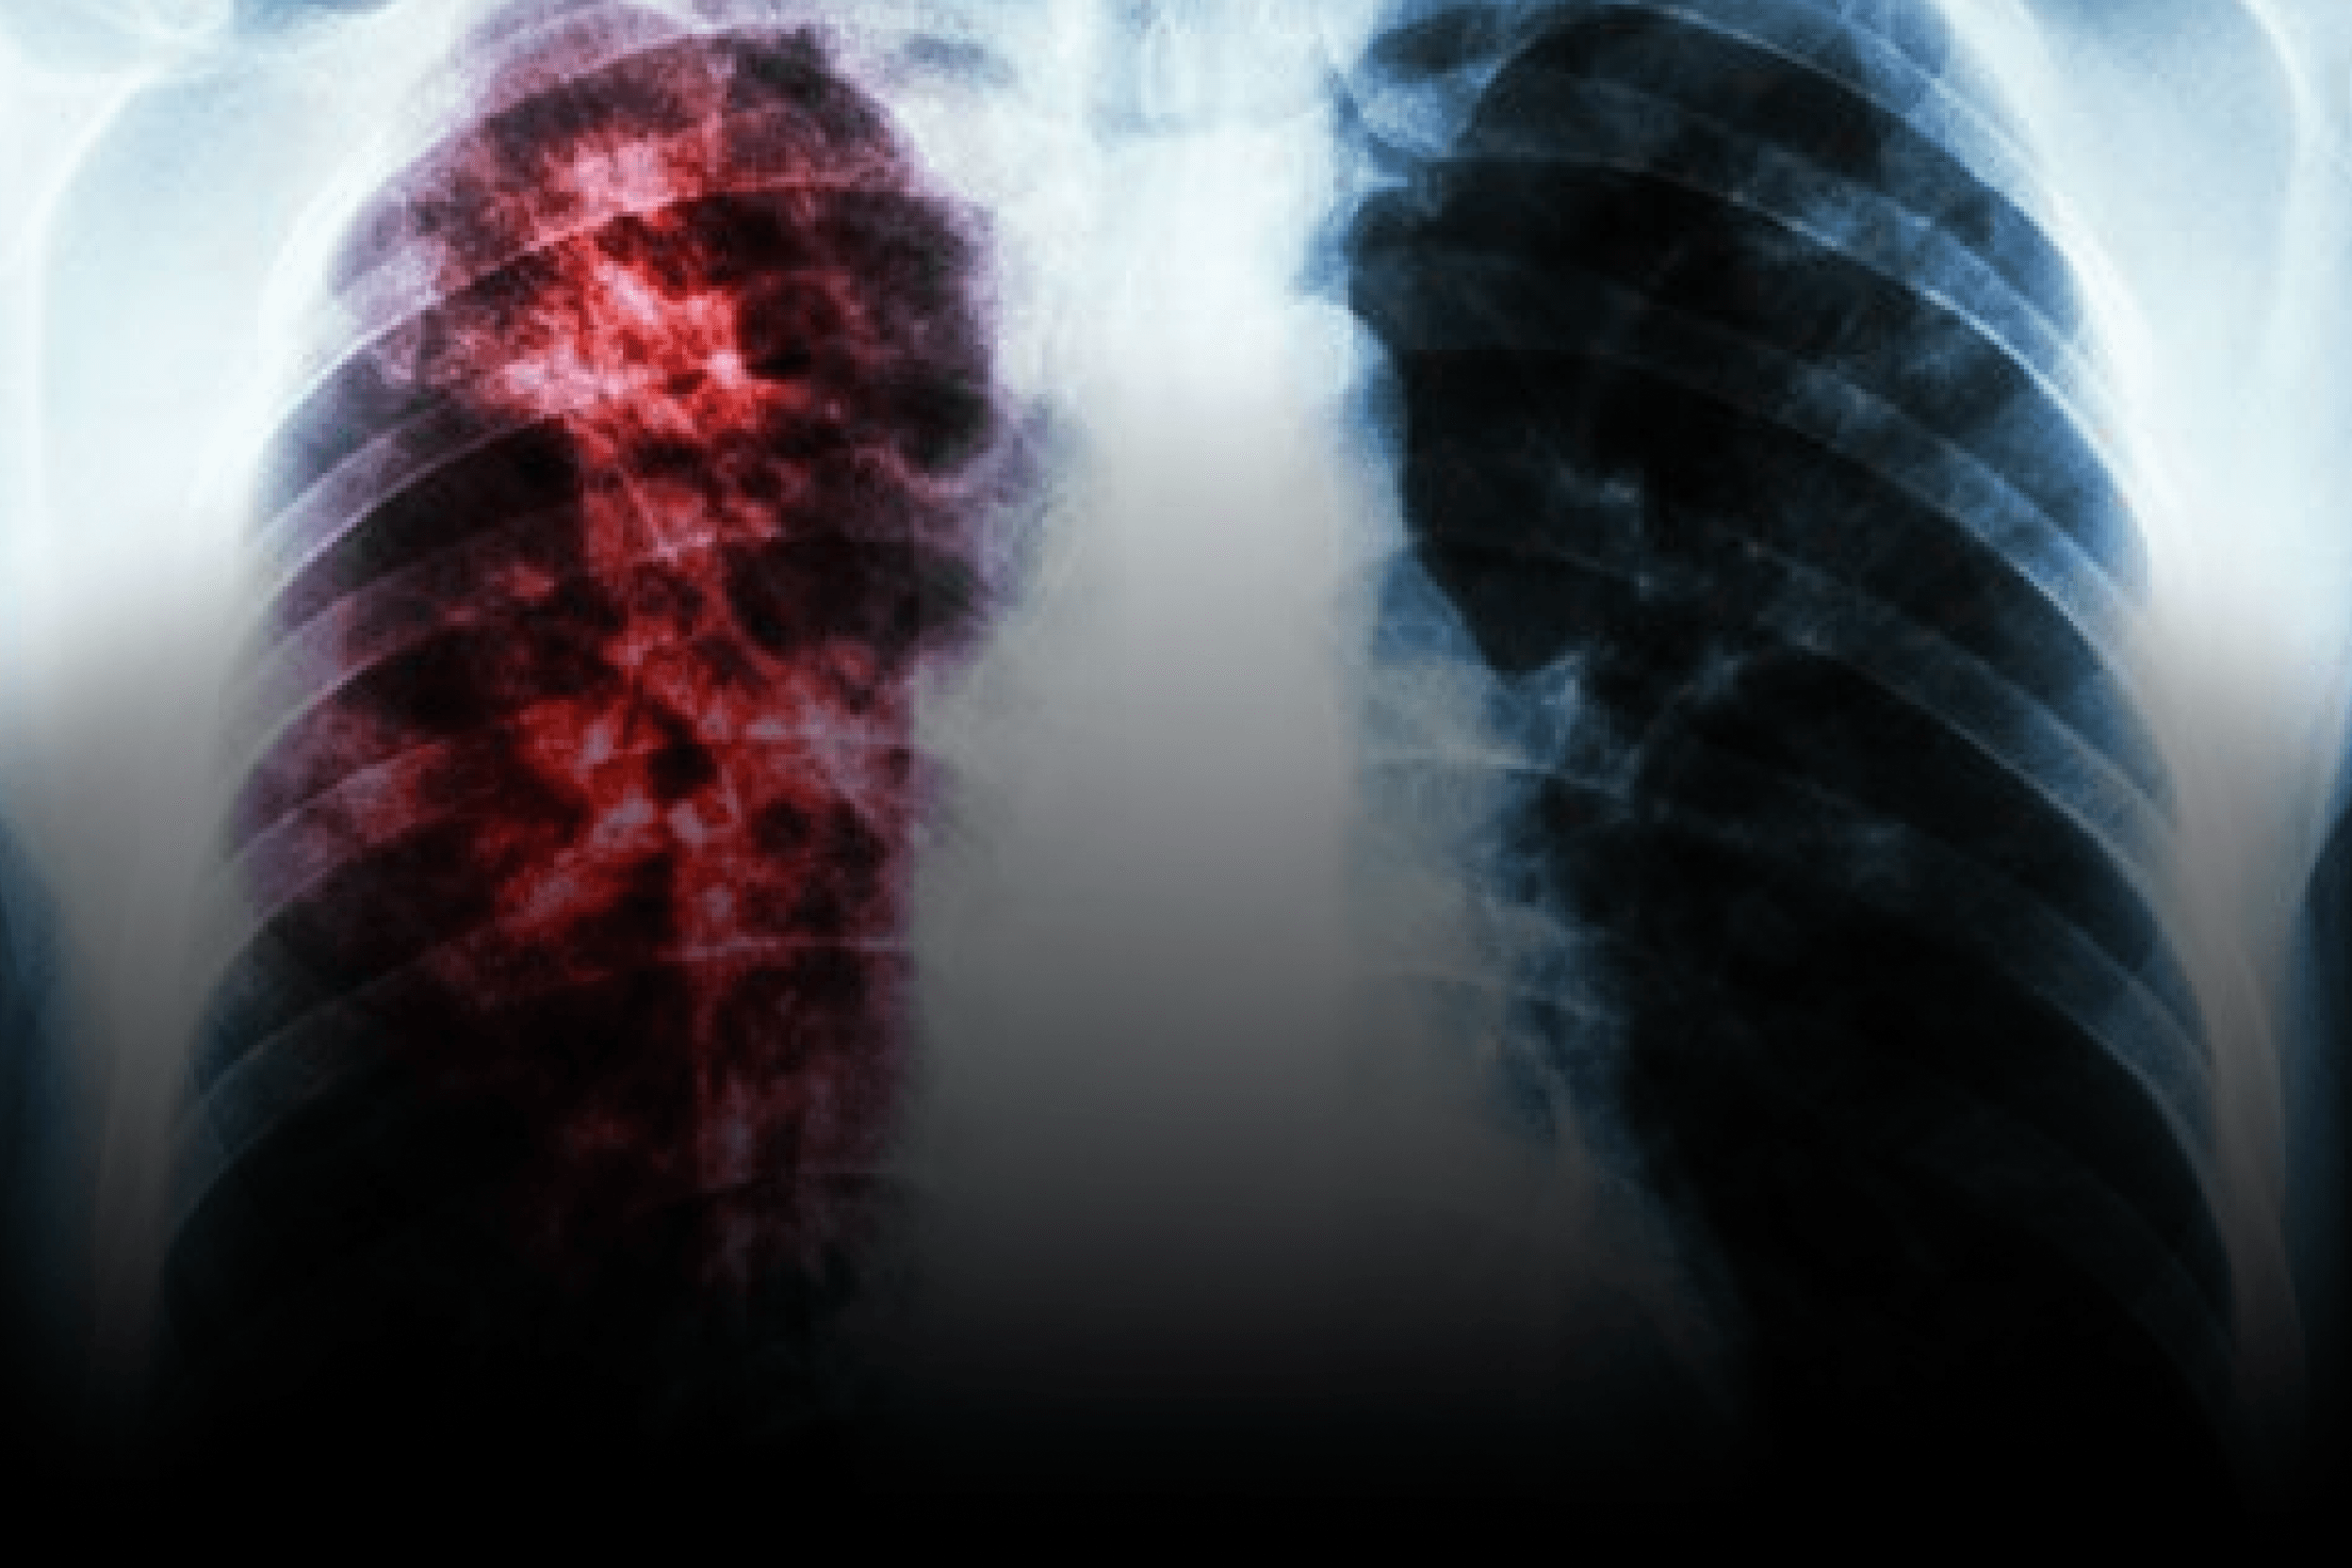

Eficácia e segurança do novo antibiótico: o que mostram os estudos

Como antecipado na introdução, os dados de fase 2 apontam que o novo antibiótico para tuberculose alcançou maior rapidez de negativação de cultura e melhor controle sintomático quando comparado ao tratamento tuberculose resistente padrão, sem aumento de eventos adversos graves. O desenho multicêntrico, apoiado por entidades dos EUA, avaliou endpoints clínicos e microbiológicos (tempo para conversão de cultura em 8–12 semanas) e um painel de segurança com foco em hepatotoxicidade, QTc e neuropatia.

Na comparação com regimes tradicionais e com esquemas totalmente orais já discutidos (ex.: BPaL), o candidato mostrou potencial para reduzir carga de comprimidos e encurtar duração total, o que beneficia especialmente pacientes com intolerância a múltiplos fármacos e comorbidades (HIV, diabetes), frequentemente sensíveis a medicamentos. Para nutricionistas e psicólogos, menor toxicidade e esquema mais simples tendem a melhorar apetite, sono e adesão — fatores críticos em desfechos de TB.